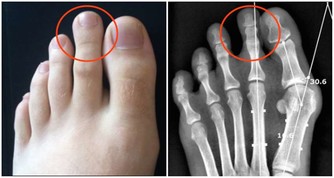

糖尿病患者體內的血糖過高,糖分是細菌的充足營養,所以糖尿病患者如果出現了皮膚上的傷口,細菌就很容易進入到傷口處並且大量的繁殖,這樣就會導致傷口由很小的面積潰破到很大的面積,這樣癒合起來就很難了。

常常有看到這樣的患者,患者本身糖尿病,血糖控制不好,導致受壓迫的部位常常潰破,有的時候,腐肉去不了,新肉也生不上來,長時間的遷延不愈,最嚴重的患者最後會有小的傷口潰破直接導致潰爛至骨頭。

這種是比較重的,很多患者相對這種程度來講,一般是達不到的,但是大眾對於糖尿病患者的皮膚破潰都沒有引起重視,這是極其錯誤的思想。

上次回老家,老家有人過來,找我看一眼手,患者手上纏著自己做的白布,膿水已經透過白布滲出來了,我打開了白布,看到裡面潰爛成一片,有兩個一元錢硬幣那麼大的傷口,患者本身是血糖高,但是患者自己吃藥又不及時,最近這段時間自己把藥停了,血糖高,又有傷口,就潰爛了。我問了病史,患者最開始的時候,只有2平方毫米那麼大的小口子,但是就是不癒合,最後發展成這麼大的。